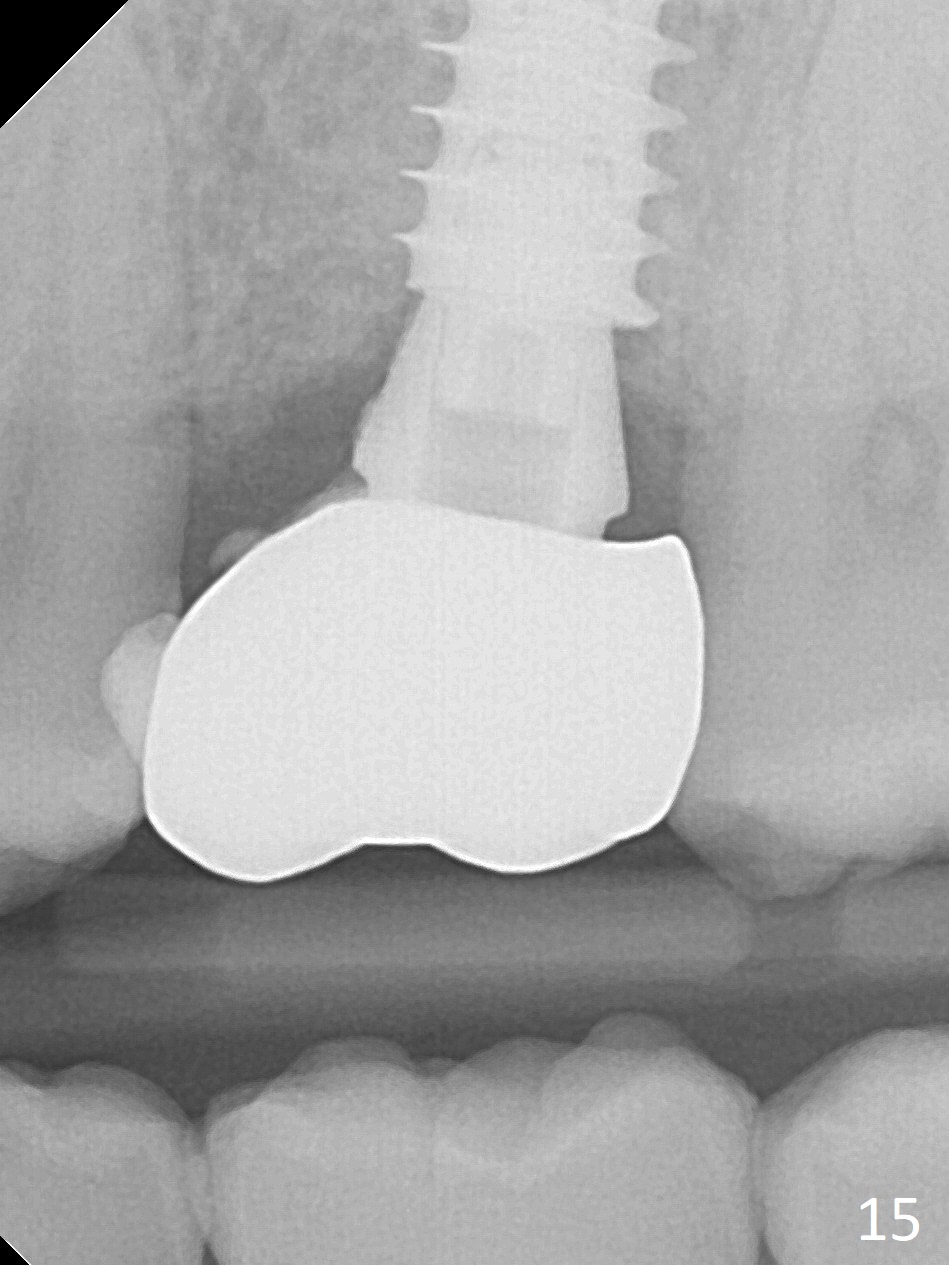

It seems that the provisional traps food. The former has been removed by the patient by the time she returns 3.5 months postop. The gingiva around the implant is healthy. The organization of the bone graft has changed (Fig.13, as compared to Fig.8,9). The implant has osteointegrated. Take photos to show the buccal and palatal gingival margin before impression. In fact the newly formed gingiva covers the margin of the abutment 5 months postop (Fig.14). Laser gingivectomy is performed prior to impression. Provisional should be kept in place with good oral hygiene. The crown dislodges 8 months post cementation, probably due to bruxism, small, short abutment and open margin (Fig.15 (taken after recementation; the residual cement is removed later)).